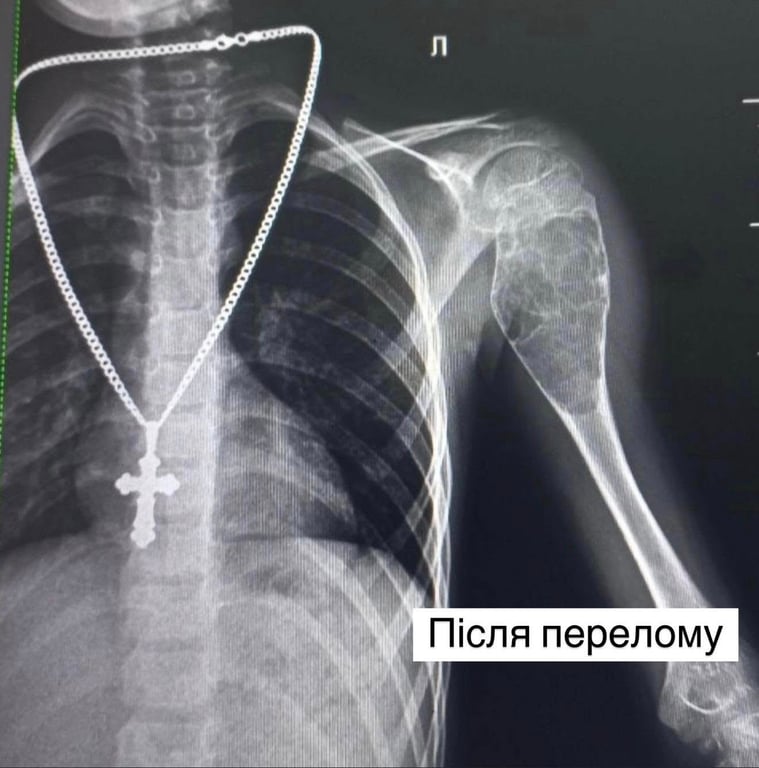

Історія хлопчика почалася ще у 2022 році після звичайного падіння під час збирання грибів. Спершу лікарі обмежились гіпсовою пов’язкою. Проте, у хлопчика знову тріснула кістка. Медики запевняли, що хлопчик "переросте" проблему. Але згодом переломи стали повторюватися — навіть легкий рух чи падіння могли призвести до нової травми. За словами матері Івана, син жив у постійному страху і тому не міг гратися, кататися на велосипеді чи підіймати навіть дуже легкі речі.

Розв’язати проблему вдалося після того, як мама звернулася до Центру дитячої медицини. Ретельна діагностика показала, що причиною ламкості кістки стало пухлиноподібне утворення — аневризмальна кіста розміром 9х4 см.

Команда ортопедів-травматологів, яку очолив Олександр Корольков, провела складне втручання. Вони виконали внутрішньокісткову резекцію, видаливши пухлину, замінили дефект аллотрансплантатами та укріпили кістку двома гнучкими титановими стержнями. Медики зауважили, що післяопераційне відновлення хлопчика проходить без гіпсу — йому зафіксували руку косинкою.

"Кістка була настільки розм’якшена, що буквально провалювалася під невеликим натиском. Ще трохи — і вона могла б зруйнуватися повністю", — розповів лікар.